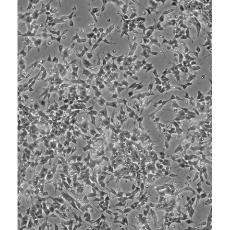

產品名稱 SH-SY5Y [SHSY-5Y]

中文名稱 人神經母細胞瘤細胞

組織來源 神經母細胞瘤;骨髓來源;男性

細胞種屬 Homo sapiens, human

生長特性 mixed, adherent and suspension

形態特征 epithelial-like and neuronal-like

細胞描述 SH-SY5Y cells have a reported saturation density greater than 1×10^6 cells/cm^2. They are reported to exhibit moderate levels of dopamine beta hydroxylase activity. Ref